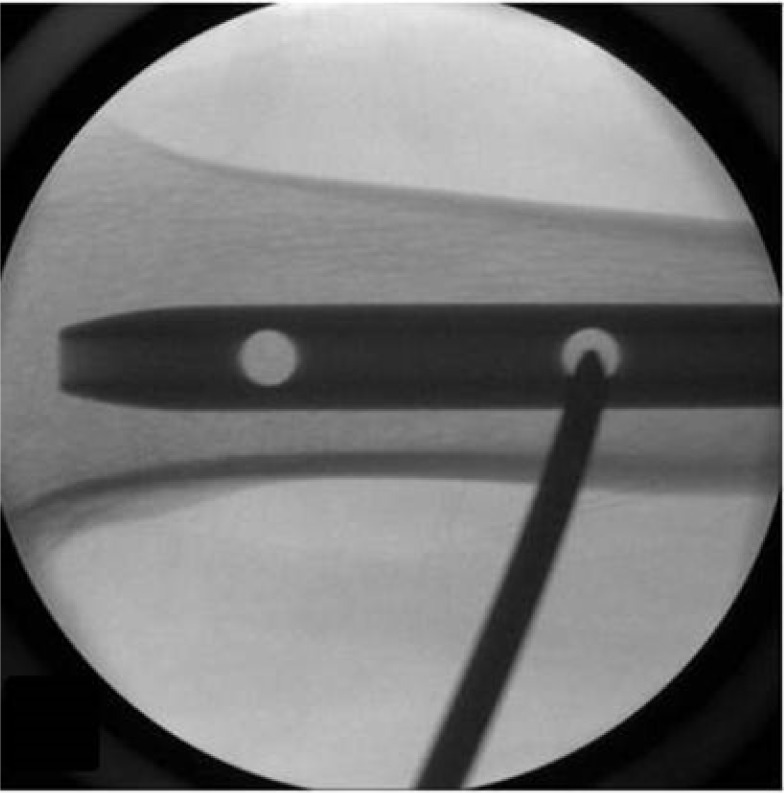

目的:准确定位远端钉孔和放置远端联锁螺钉是髓内钉的挑战。本研究提出了一种使用Steinmann销直接置入远端锁定螺钉的技术,无需重新定位销或钻头。方法:采用18个锯骨股骨模型和髓内钉。一名第一年住院医师在每个模型上创建了两个远端锁定孔,采用传统的徒手技术和一种新的方法,在图像增强下使用Steinmann销和锤子。这些技术基于三个参数进行评估:(1)创建远端锁定孔所需的时间,从针定位在孔中心的那一刻开始测量,直到远端皮质穿过联锁孔;(二)用个人伽马辐射剂量计估算的辐射剂量(单位:毫雷姆/小时);(3)失败次数,定义为在近皮层和远皮层上造成一个以上的洞。结果:与传统方法相比,新方法的放射剂量更低(P=0.0268),失败次数更少(P=0.0367)。此外,与传统方法相比,使用新技术建立远端孔所需的时间更短(P=0.0217)。结论:采用Steinmann销锤制作远端联锁孔准确、高效、经济。

Objectives: Accurately targeting distal nail holes and placing distal interlocking screws pose challenges during intramedullary nailing. This study proposes a straightforward technique for distal locking screw insertion using a Steinmann pin, eliminating the need to reposition the pin or drill bit. Methods: We utilized 18 Sawbones femur models and intramedullary femur nails. A first-year resident created two distal locking holes on each model, employing both the conventional freehand technique and a novel method involving a Steinmann pin and hammer under image intensification. These techniques were evaluated based on three parameters: (1) the time required to create distal locking holes, measured from the moment the pin was positioned at the center of the hole until the far cortex was drilled through the interlocking hole; (2) the radiation dose (in mrem/h), as estimated with a personal gamma radiation dosimeter; and (3) the number of failures, defined as the creation of more than one hole in the near and far cortex. Results: The new technique was associated with a lower radiation dose (P=0.0268) and fewer failures (P=0.0367) than the conventional approach. Additionally, the time required to establish distal holes was shorter using the new technique compared to the conventional method (P=0.0217). Conclusion: The creation of distal interlocking holes with a Steinmann pin and hammer is accurate, efficient, and cost-effective.